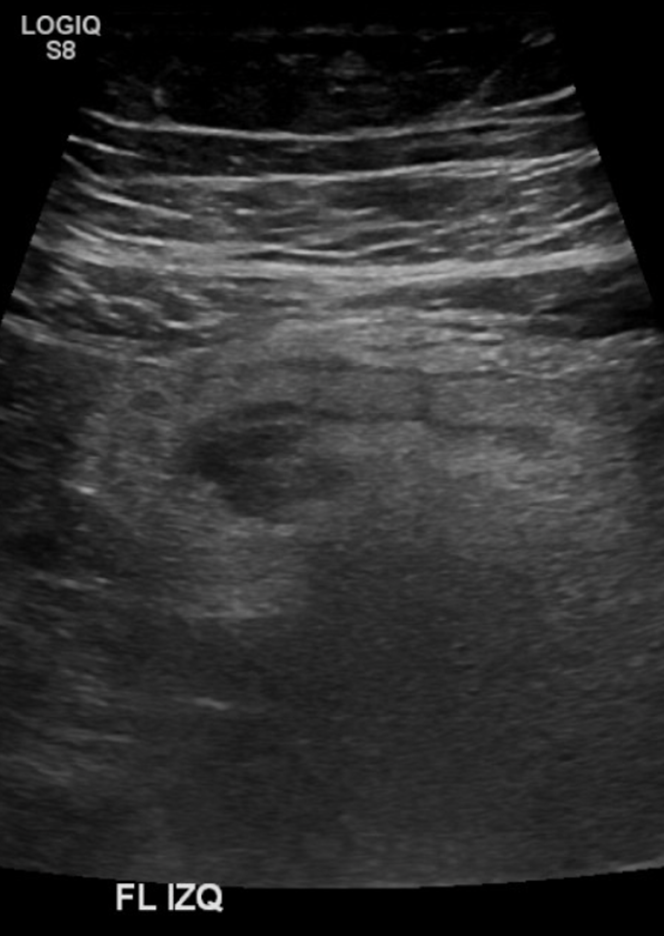

Examen limitado por meteorismo. Páncreas parcialmente visualizado. Hígado aumentado de ecogenicidad con área de respeto periportal sugerente esteatosis difusa moderada. En región dolorosa en FII se observa imagen pseudonodular hipoecogénica, con aumento de ecogenicidad de la grasa adyacente, sin relación intestinal evidente, sugerente apendagitis epiploica.

Hallazgos ecográficos sugerentes de apendicitis epiploica a nivel del flanco izquierdo. Cambios de esteatosis hepática leve. Resto del estudio ecográfico abdominal sin hallazgos significativos.